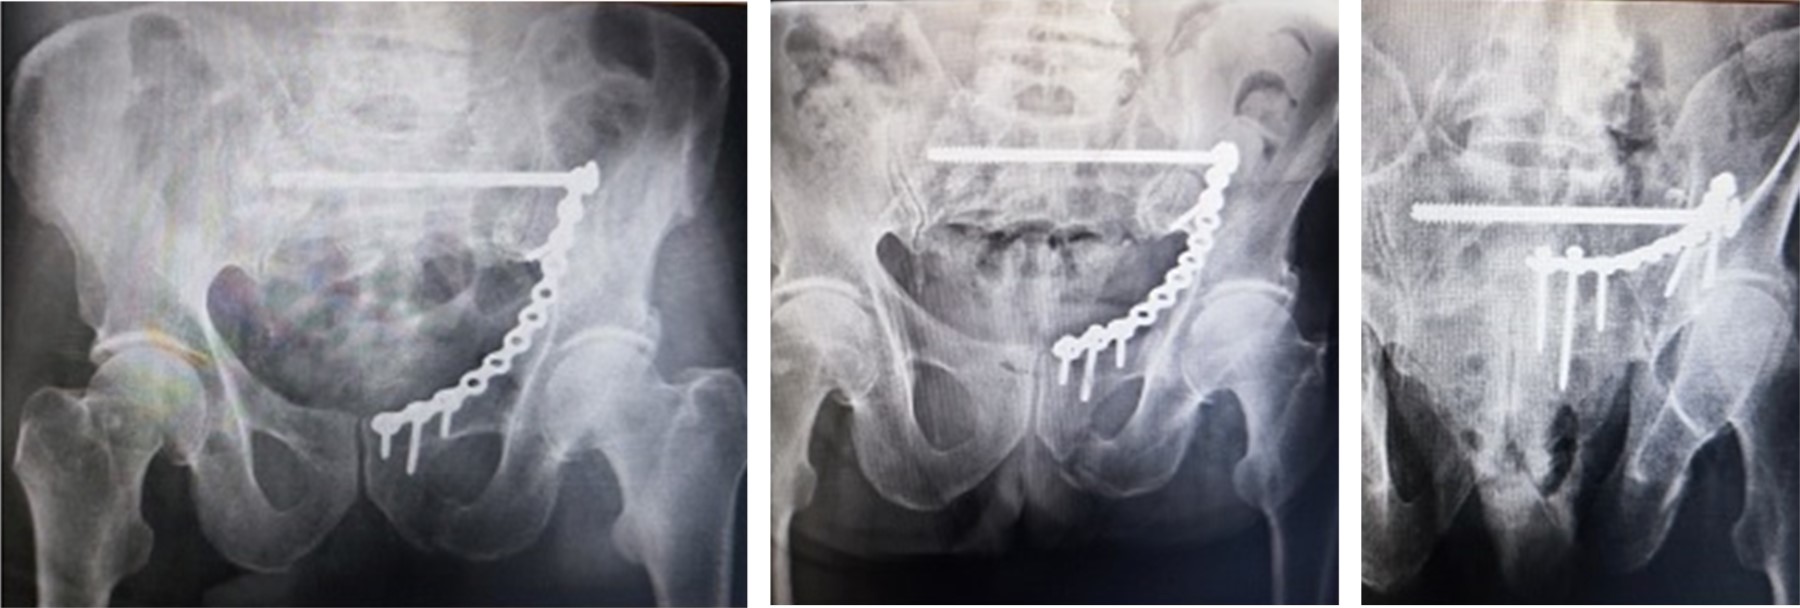

Mecánicas (Figura 4): aflojamiento del material de osteosíntesis en tres pacientes. Caso 1: femenina, 67 años (61C3.2); caso 2: femenina de 75 años (61B2.2); caso 3: masculino de 72 años (61B2.2), los tres por accidente de tránsito.

A pesar de la migración, las fracturas consolidaron, dos se reintegraron a actividades de la vida cotidiana con asistencia de bastón, una ameritó extracción del material de osteosíntesis.